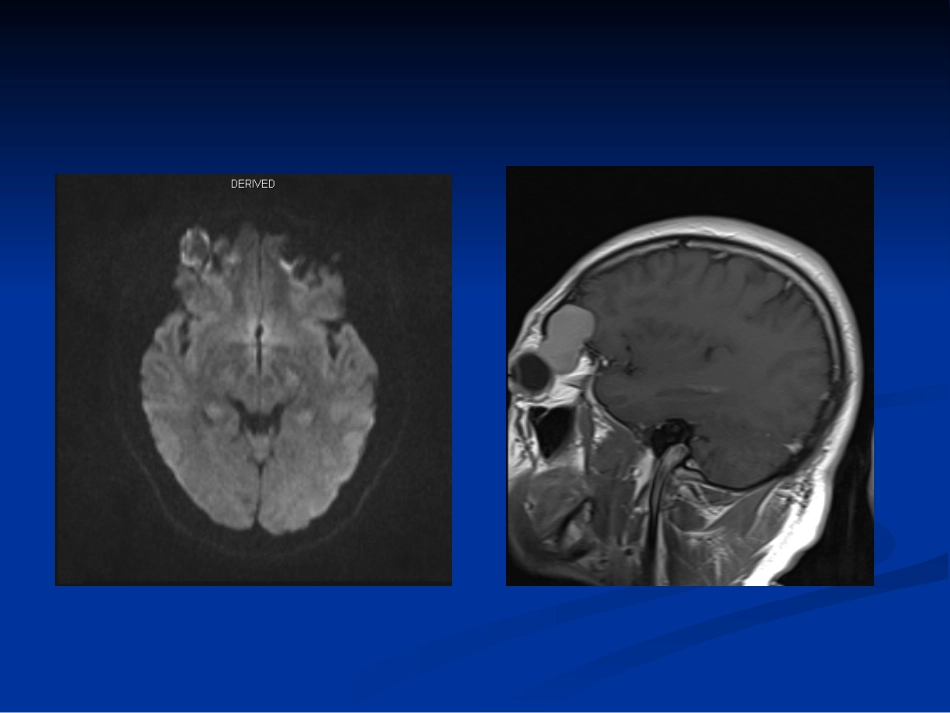

今日读片今日读片ID:1005377965ID:1005377965影像资料:影像资料:2016-8-12016-8-1日头颅日头颅MRIMRI平扫平扫++增强增强2016-8-22016-8-2日头颅日头颅CTACTA患者男性,患者男性,3737岁岁临床病史:临床病史:入院前三个月,无明显诱因下出现右眼入院前三个月,无明显诱因下出现右眼干涩不适,就诊于当地医院眼科,自诉查眼球未干涩不适,就诊于当地医院眼科,自诉查眼球未见明显异常,予以对症治疗,症状有所缓见明显异常,予以对症治疗,症状有所缓解,解,20162016年年66月开始,自觉右眼较前明显突出,月开始,自觉右眼较前明显突出,伴有视物重影,自行调节后可缓解,同时伴有视伴有视物重影,自行调节后可缓解,同时伴有视力下降。在当地医院行力下降。在当地医院行CTCT检查提示右侧额、眼检查提示右侧额、眼眶外侧壁膨胀性骨质破坏,病变向颅内及眼眶内眶外侧壁膨胀性骨质破坏,病变向颅内及眼眶内突起。既往突起。既往20002000年因近视眼行激光手术治疗。年因近视眼行激光手术治疗。2016-8-12016-8-1头颅头颅MRIMRI2016-8-2头颅CT阅片思路阅片思路临床特征临床特征影像学特征(定位、定性)影像学特征(定位、定性)临床特征:临床特征:中年男性患者;中年男性患者;病程较长;不适感逐渐发展疼痛感;伴有病程较长;不适感逐渐发展疼痛感;伴有视力减退改变;有近视眼激光手术史。视力减退改变;有近视眼激光手术史。影像学分析思路部位、大小、信号(密度)、形态、数量、周围情况邻近解剖结构改变:大小与形态异常、密度或信号异常、位置异常、眶壁骨质异常、眼眶通道异常、肿块定位:主要位于右眼眶外上限,眶骨膜下间隙内,并向颅内延伸定位:主要位于右眼眶外上限,眶骨膜下间隙内,并向颅内延伸定位:定位:MRIMRI征象:位于眼外肌外侧、长圆形、眼球偏突、征象:位于眼外肌外侧、长圆形、眼球偏突、眼外肌内移、视神经移位明显。眼外肌内移、视神经移位明显。CTCT征象:眼眶外侧壁及右侧额骨局部骨质膨胀性征象:眼眶外侧壁及右侧额骨局部骨质膨胀性改变改变定性(良定性(良//恶性):恶性):良、恶性的主要鉴别要点良、恶性的主要鉴别要点病灶的大小、边界;病灶的大小、边界;与周围组织关系(推压、侵犯);与周围组织关系(推压、侵犯);有无远处转移。有无远处转移。此病例的影像学主要特征此病例的影像学主要特征MRIMRI:病灶边界清晰,其内信号欠均匀(:病灶边界清晰,其内信号欠均匀(T1WIT1WI呈稍高信号,呈稍高信号,T2WIT2WI呈呈高信号,混杂不均匀等信号,周围可见低信号环形影),在高信号,混杂不均匀等信号,周围可见低信号环形影),在DWIDWI边边缘呈不均匀高信号,其中心呈稍低信号,邻近眼球、泪腺及上直肌、外缘呈不均匀高信号,其中心呈稍低信号,邻近眼球、泪腺及上直肌、外直肌受压、推移。直肌受压、推移。CTCT:右侧眼眶外侧壁及右侧额骨骨质局部膨胀改变;病灶边缘可见环形:右侧眼眶外侧壁及右侧额骨骨质局部膨胀改变;病灶边缘可见环形骨化影。骨化影。病灶周围脂肪间隙清晰,增强检查病灶未见强化。病灶周围脂肪间隙清晰,增强检查病灶未见强化。结合临床综合考虑:结合临床综合考虑:良性病变,来源于肌锥外间隙或骨膜下间隙良性病变,来源于肌锥外间隙或骨膜下间隙肌锥外间隙病变:肌锥外间隙病变:泪腺肿瘤、转移瘤、淋巴瘤、泪腺肿瘤、转移瘤、淋巴瘤、神经鞘瘤神经鞘瘤、、炎性假瘤(局炎性假瘤(局限性肿块型)、静脉曲张限性肿块型)、静脉曲张骨膜下间隙病变:骨膜下间隙病变:血肿血肿、、皮样囊肿皮样囊肿、、表皮样囊肿表皮样囊肿神经鞘瘤神经鞘Schwann细胞增殖形成的一种良性肿瘤,占眶内肿瘤的1%~3%可发生于各种年龄,但以20~70岁成年人居多,男女发病率相仿多为单发影像学表现多为类圆形或椭圆形,也可以为哑铃状或串珠状,长径与眼眶长轴一致,边界清楚。CT平扫肿瘤密度与视神经和眼外肌接近,其内可见低密度囊变区,少数肿瘤可见钙化灶。增强肿瘤实性部分呈中等度强化,较均匀,囊变区不强化。肿瘤生长缓慢,成膨胀性生长,可压迫视神经、眼外肌移位。MRI表现...